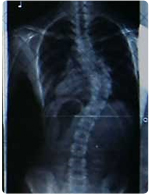

61度 ![]() |

46度 ![]() |

32度

15度